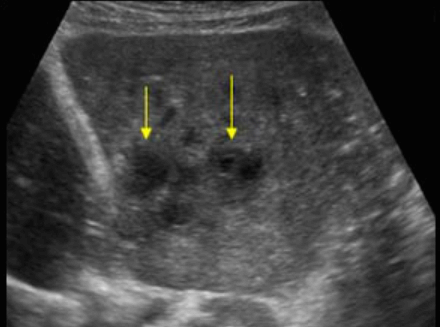

US finding

- 원형으로 경계가 분명한 단순낭종이다.

- 큰 낭종 안에 작은 낭종이 존재(daughter cyst)

- 낭종벽내 석회화가 관찰된다 (cyst wall calcification)

- 백합모양(water-lily sign)

daughter cyst and water-lily sign ②아메바성 간농양 (amoebic abscess)